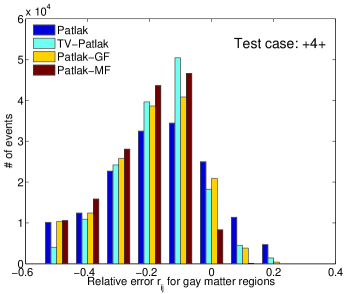

In figure 5 we illustrate the relative error of noisy case for gray matter regions in the phantom, including frontal lobes, occipital lobes, insula cortex, temporal lobes and globus pallidus, which are of interest for Alzheimer’s disease research. The error bars show that all estimation methods for gray matter regions have negative bias and there are fewer cases with high error by TV-Patlak.